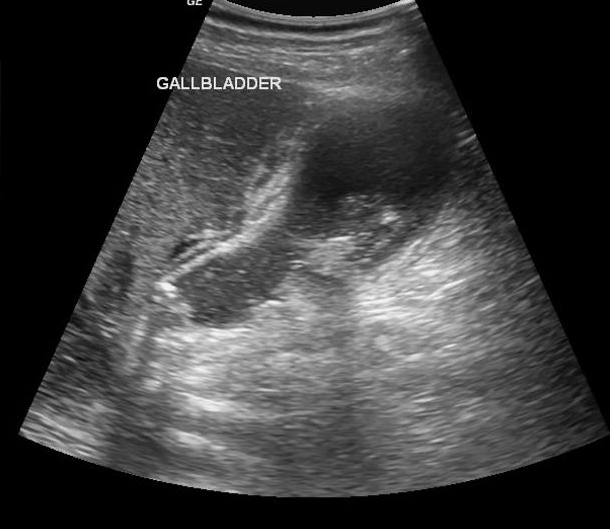

Cholecystite aigue

lithiasique : Images echographique de calcul

vesiculaire avec cone de hypoascoustique posterieure

. Distendue de la vesicule biliaire et epaissisement

de sa paroi . La contenue de la vesicule est

irreguliee . |